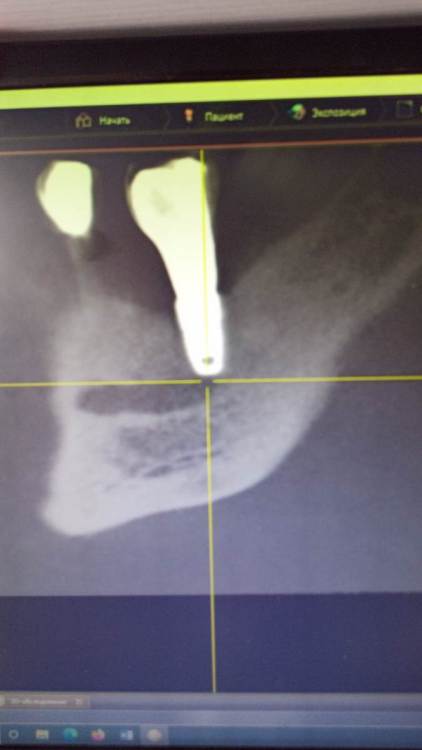

DoctorT Опубликовано 2 февраля, 2024 Поделиться Опубликовано 2 февраля, 2024 01.02.2024 в 08:36, Зндрю сказал: Три года назад слева снизу поставили два импланта : 4 и 6. Через 4 месяца на них установили две коронки. 4-ка работает лучше родного зуба, претензий нет. 6-ка под нагрузкой приводит к сильной боли , после снятия коронки боль уходит и в заглушенном состоянии имплант не тревожит. Проходил обследование на гальваноз и неврологию нижней ветви тройничного нерва - диагнозы не подтвердились . Другие имплантологи говорят, что боли в 6-ке возникают из-за нарушения пропорции корневой и коронковой частей конструкции. Установивший имплант хирург отрицает возможность переимплантации данной конструкции, объясняя, что кость слева снизу слишком тонкая и предлагает просто поставить заглушку на этот имплант и оставить всё как есть . Меня такой расклад не устраивает, хотелось бы на этом месте иметь полноценные жующие зубы со 100-% контактом с верхними зубами ( сверху напротив установлен цельнолитой мост ). Прошу совета, как мне быть - настаивать на удалении одного (или обоих) имплантов с последующей подложкой кости и переимлантацией, либо возможно проблемный имплант закрыть заглушкой и смоделировать другую конструкцию без удаления винтов и подложки кости ? Спасибо за ответы по существу. Если черным нарисован нижнечелюстной канал, то это не он, канал значительно ниже. Мне кажется, нужно поменять профиль прорезывания (придесневую часть коронки) и все должно пройти. Ссылка на комментарий

Зндрю Опубликовано 2 февраля, 2024 Автор Поделиться Опубликовано 2 февраля, 2024 (изменено) КТ имеется . Окончание импланта лежит на нижней ветви тройничного нерва, но не травмирует его. Со слов независимого имплантолога, у которого был на консультации, иначе симптомы были бы неврологические , а их нет . Изменено 2 февраля, 2024 пользователем Зндрю Ссылка на комментарий

АнтонТЛТ Опубликовано 3 февраля, 2024 Поделиться Опубликовано 3 февраля, 2024 Мне не нравится поддесневой профиль коронки Ссылка на комментарий

Doc Опубликовано 3 февраля, 2024 Поделиться Опубликовано 3 февраля, 2024 Коллеги правильно говорят. Похоже что проблема в той части коронки, которая давит на десну и кость под нею. За это говорит еще и тот факт, что без коронки ничего не болит. Попробуйте с врачом изменить форму нижней части коронки. Ссылка на комментарий

kramer Опубликовано 7 февраля, 2024 Поделиться Опубликовано 7 февраля, 2024 В принципе понятно. Лично мое мнение, что надо удалять оба имплантата (ближний выглядит недозаглубоенным (плохо видно), дальний слишком близко к нерву, что скорее всего и дает симптомы. Установить новые импланты, сделать мостовидную конструкцию. Ссылка на комментарий